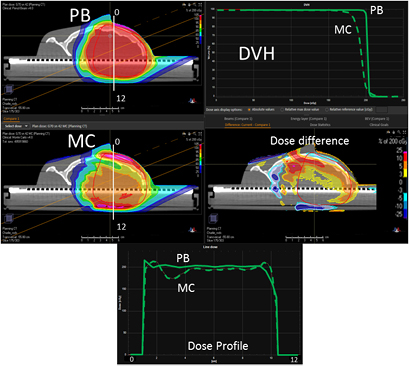

Figure 6 reports the PB dose distribution of a plan optimized on the two slabs of the head phantom and its MC recalculation.

Figure 6. PB optimized dose distribution on the 2/6 head phantom (top left) and MC recalculation (middle left) with a proton field angle of 70° and the RS 42 cm from the isocenter (i.e. air gap ~26 cm). The white lines represent the dose profiles' (bottom) extraction plans. On the right side of the figure, the DVHs of both the dose distributions (top right) and dose difference (middle right) are displayed.

Standard image High-resolution imageThe dose differences between the PB and MC are less pronounced for this configuration compared to the previous one (figure 7 and table 2). Again, it is worth noting that the MatriXX plane of measurement was not placed in the region where the largest disagreement occurs (figure 6).

Figure 7. Dose distribution and γ analysis comparison between the MatriXX measurement and the PB or MC dose engine in a transversal plane for the 2/6 head phantom with a gantry angle of 70° and a snout position at 42 cm. The white lines represent the dose profiles' extraction plans, the red lines are the measured data profile while the green lines represent the calculated dose distribution. The red region in the γ graph represents the area with γ > 1.